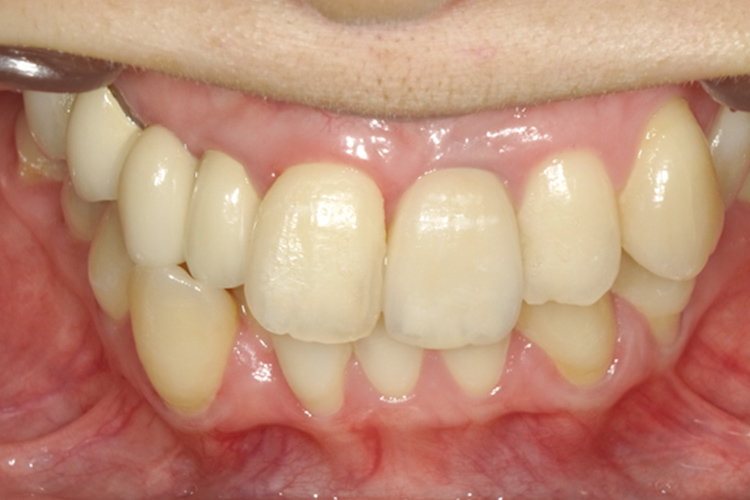

治療前

治療後